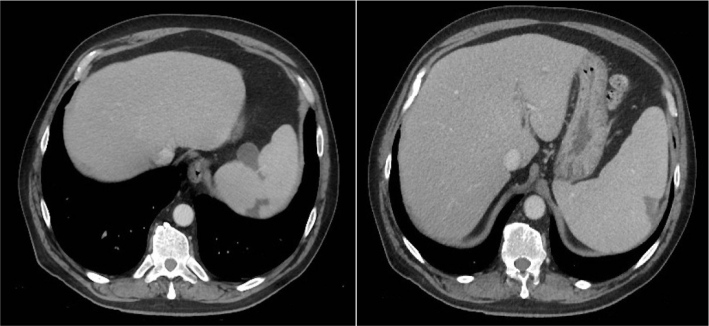

Case description: We describe the case of a 56-year-old previously healthy man who presented with fever and abdominal pain. Abdominal computed tomography (CT) revealed splenomegaly and multiple wedge-shaped splenic infarcts. During admission, the patient developed transient disorientation, and cerebrospinal fluid analysis was consistent with aseptic meningitis. Serological and molecular testing confirmed acute EBV infection in blood, pharyngeal swab and cerebrospinal fluid. No underlying prothrombotic condition was identified. The patient recovered completely with supportive care, without the need for antiviral treatment or anticoagulation.